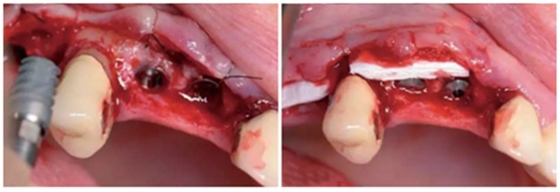

圖14:放置了3顆RatioPlant Avantgarde (HumanTech Germany)種植體。

圖15:放置Geistlich Mucograft®膠原基質(zhì)(Geistlich Pharma)來支撐軟組織。

圖16:種植后4個月,放射線檢查RatioPlant種植體的骨結(jié)合情況。